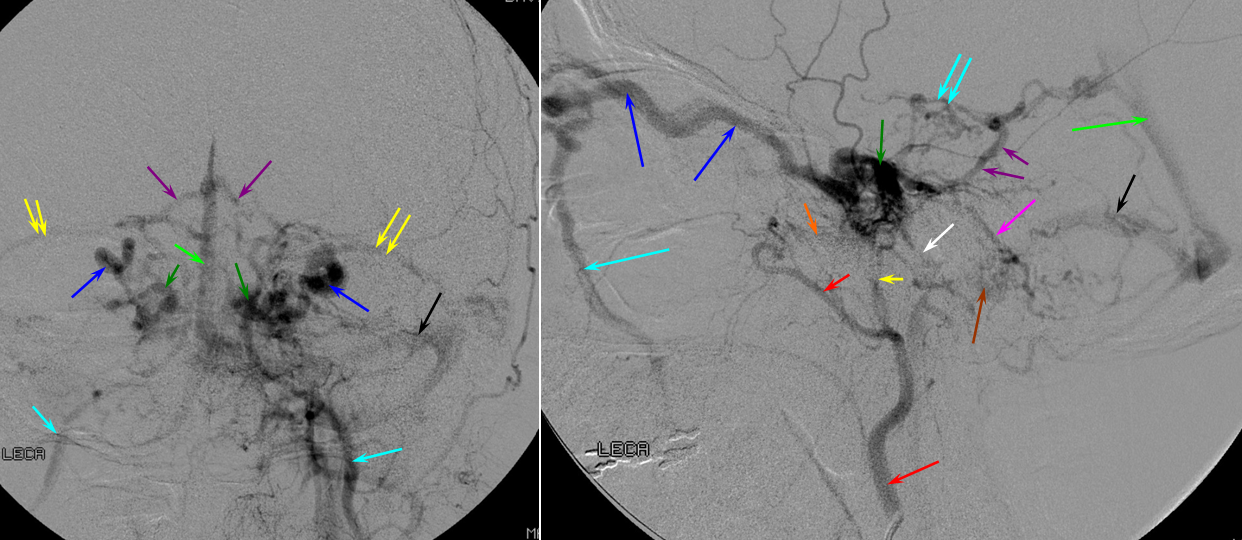

Below is an example of as large an inferior sagittal sinus (white) as one is likely to ever see under non-pathologic circumstances. Why is this sinus so large? Again, the answer is that veins are like rivers — the inferior sagittal sinus happens to be receiving a completely benign, nonpathologic mesial anterior frontal vein (blue arrows). However, the increased inflow into the Galen system has likely resulted in alternate drainage of the basal vein (purple) into the superior petrosal sinus via the lateral mesencephalic vein (black) — see deep venous system and veins of posterior fossa pages for more info. Also notice a large emissary vein (pink)

Blue Circle=tumor blush. The superficial Sylvian vein is prominent within the circle and extends over the temporal lobe towards the superior petrosal sinus (dark blue arrow). Labbe=black. No Trolard is seen, various superior cortical veins drain into the SSS. Basal vein=light blue, dominant posterior drainage. Very nice demonstration of the deep venous system tributaries. Anterior Septal vein=bright green, capturing territory of hypoplastic anterior cerebral vein. The inferior sagittal sinus is absent. Thalamostriate vein with large longitudinal caudate vein=yellow. Direct lateral vein=pink. Posterior caudate/splenial veins=brown. A prominent Pericallosal Vein empties into a large inferior sagittal sinus. Also note hypoplasia of the superior sagittal sinus proximal to a large superior frontal convexity tributary.

Dark blue=percallosal vein. Light blue=inferior sagittal sinus. Pink=frontal convexity vein. Orange=anterior septal vein. Yellow=thalamostriate vein. Red=Internal cerebral vein. Occipital sinus (blue arrows on the sagittal and MRI axial projections), draining into the marginal sinus (dark blue arrows on the AP projections.) The occipital sinus is more commonly seen in children.